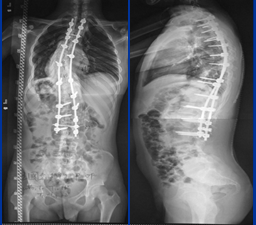

第二次手术:侧凸矫正。患者外观畸形改善明显,身高继续增加5cm。

术后照片